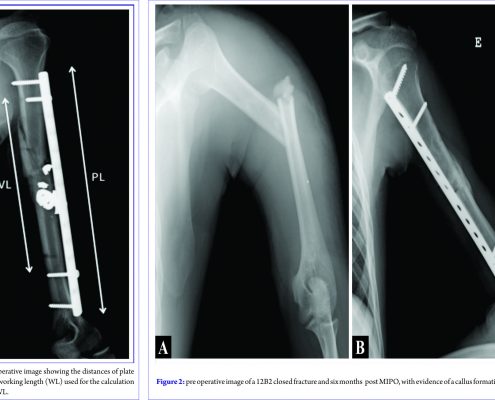

MIPO for Humeral Shaft Fractures: Correlation between Radiographic, DASH, and SF-12 results